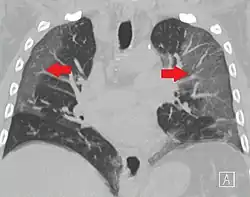

High-resolution CT image showing ground-glass opacities in the periphery of both lungs in a patient with COVID-19 (red arrows). The adjacent normal lung tissue with lower attenuation appears as darker areas.

CT image in patient with COVID-19 showing bilateral ground-glass opacities at the periphery of both lungs.

Several studies have described a pattern among initial, intermediate, and hospital discharge imaging findings in the disease course of COVID-19. Most commonly, initial CT imaging reveals bilateral GGOs at the periphery of the lungs. During initial stages, this is most often found in the lower lobes, although involvement of the upper lobes and right middle lobe has also been reported early in the disease course.[16][18] This is in contrast to the two similar coronaviruses, SARS and MERS, which more commonly involve only one lung on initial imaging.[19][20] As the COVID-19 infection progresses, GGOs typically become more diffuse and often progress to consolidation.[11][18] This is sometimes accompanied by the development of a crazy paving pattern and interlobular septal thickening.[18] In many cases the most severe pulmonary CT abnormalities occurred within 2 weeks after symptoms began.[17] At this point, many individuals begin showing resolution of consolidation and GGOs as symptoms improve. However, some patients have worsening symptoms and imaging findings, with further increase in septal thickening, GGOs, and consolidation. These patients may develop lung "white-out" with progression to acute respiratory distress syndrome (ARDS) requiring treatment escalation.[17][21]